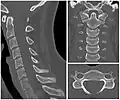

Cervical degenerative changes arise from conditions such as spondylosis, stenosis of intervertebral discs, and the formation of osteophytes. The changes are seen on radiographs, which are used in a grading system from 0–4 ranging from no changes (0) to early with minimal development of osteophytes (1) to mild with definite osteophytes (2) to moderate with additional disc space stenosis or narrowing (3) to the stage of many large osteophytes, severe narrowing of the disc space, and more severe vertebral end plate sclerosis (4).[5][6][7]

X-ray of cervical vertebrae -